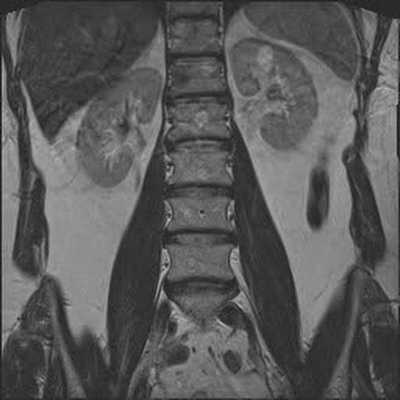

В первом учреждении использовался локатор на весь позвоночник, Т1-, Т2-, STIR-взвешенные изображения в сагиттальной плоскости, Т2-взвешенные изображения в коронарной плоскости (рис. 1). Исследование выполнялось на аппарате Рhilips Intera 1.5Т. Технические параметры импульсных последовательностей представлены в таблице. Технические параметры импульсных последовательностей для МРТ поясничного отдела позвоночника

Рис. 1. МРТ поясничного отдела позвоночника, позиционирование плоскостей. а — позиционирование локатора на весь позвоночник; б — позиционирование сагиттальной плоскости.

Рис. 1. МРТ поясничного отдела позвоночника, позиционирование плоскостей. в — позиционирование аксиальной плоскости; г — позиционирование коронарной плоскости.

Локатор на весь позвоночник использовался только для подсчета количества позвонков. В коронарной плоскости, как правило, использовались Т2-взвешенные изображения, однако при подозрении на недегенеративную спондилоартропатию (например, анкилозирующий спондилоартрит) вместо Т2-последовательности мог быть использован STIR для поиска очагов отека костного мозга в боковых массах крестца и в телах подвздошных костей. Т2-взвешенные изображения в аксиальной плоскости выполнялись единым блоком (около 30 срезов) с включением в зону сканирования не менее 3 межпозвонковых дисков с последующей реконструкцией по плоскости каждого диска (рис. 2). Рис. 2. Реконструкция по плоскости диска из блока аксиальных срезов. При необходимости в рамках одного сбора данных добавлялись короткие блоки по 2—5 срезов на неизмененные сегменты.